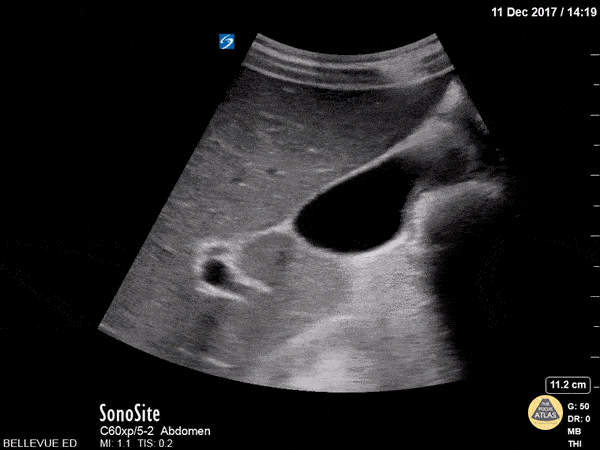

Here we see a normal anatomic variant: the right hepatic artery (small perfectly round vessel in cross section) runs superior to the CBD (seen in long axis towards the end of the clip). Hannah Kopinksi and Dr. Lindsay Davis - NYU Emergency Medicine